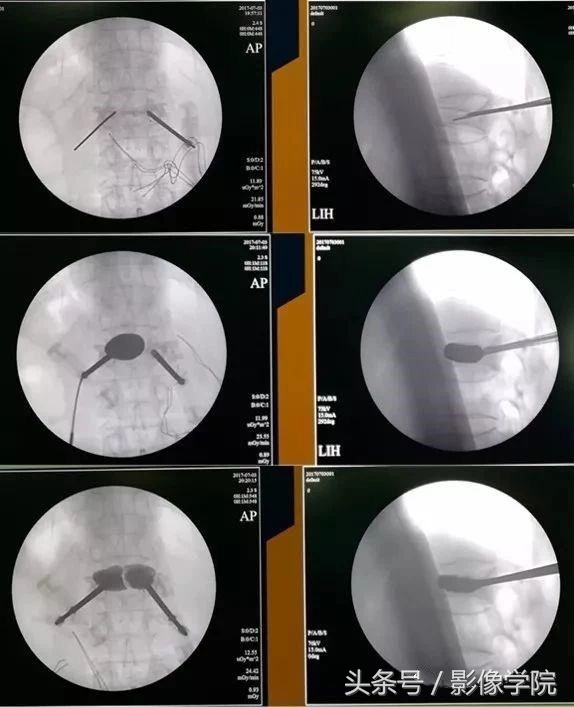

后凸成形术是在经皮椎体成形术的基础上,先用特制的气囊将压缩椎体复位,然后在低压下注入骨水泥,相比PVP可以明显减少渗漏,具有增强稳定性、止疼、恢复身高的优点。

病例演示:老年女性患者,轻微外伤后出现胸背部疼痛不适

MRI提示胸12椎体新鲜骨质疏松性压缩骨折,诊断明确后局部麻醉下行经皮椎体后凸成形术(PKP)

术后即刻患者胸背部的疼痛明显缓解,床上可自由翻身,2小时后下地自由活动,疼痛明显减轻,术后3天患者即可出院。